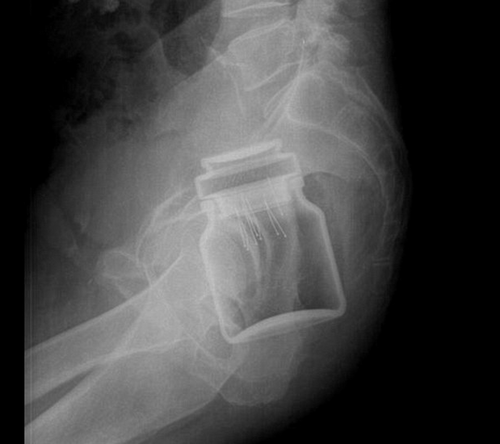

Una mención especial merece la colección de radiografías correspondientes a elementos extraños insertados voluntariamente en el cuerpo, como botes de desodorante, botellas de bebida energética, frutas y verduras o hasta un huevo son algunos de los casos que los autores de la Radiopaedia han compartido.

Aquí el bote con alfileres. ¿A quién se le ocurre?